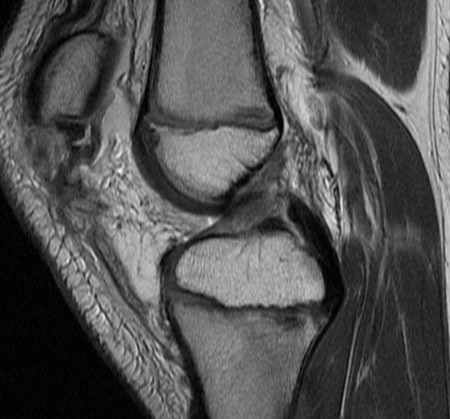

Trampoline injury, 10y/o

Wheeless: mechanism: eccentric contraction of the quadriceps on the flexed knee. occurs when the inferior pole of the patella of a child or adolescent is pulled off together with a large amount of articular cartilage and retinaculum. Superior patella pulled superiorly with chondral defect. Reference article.

Patellar sleeve avulsion